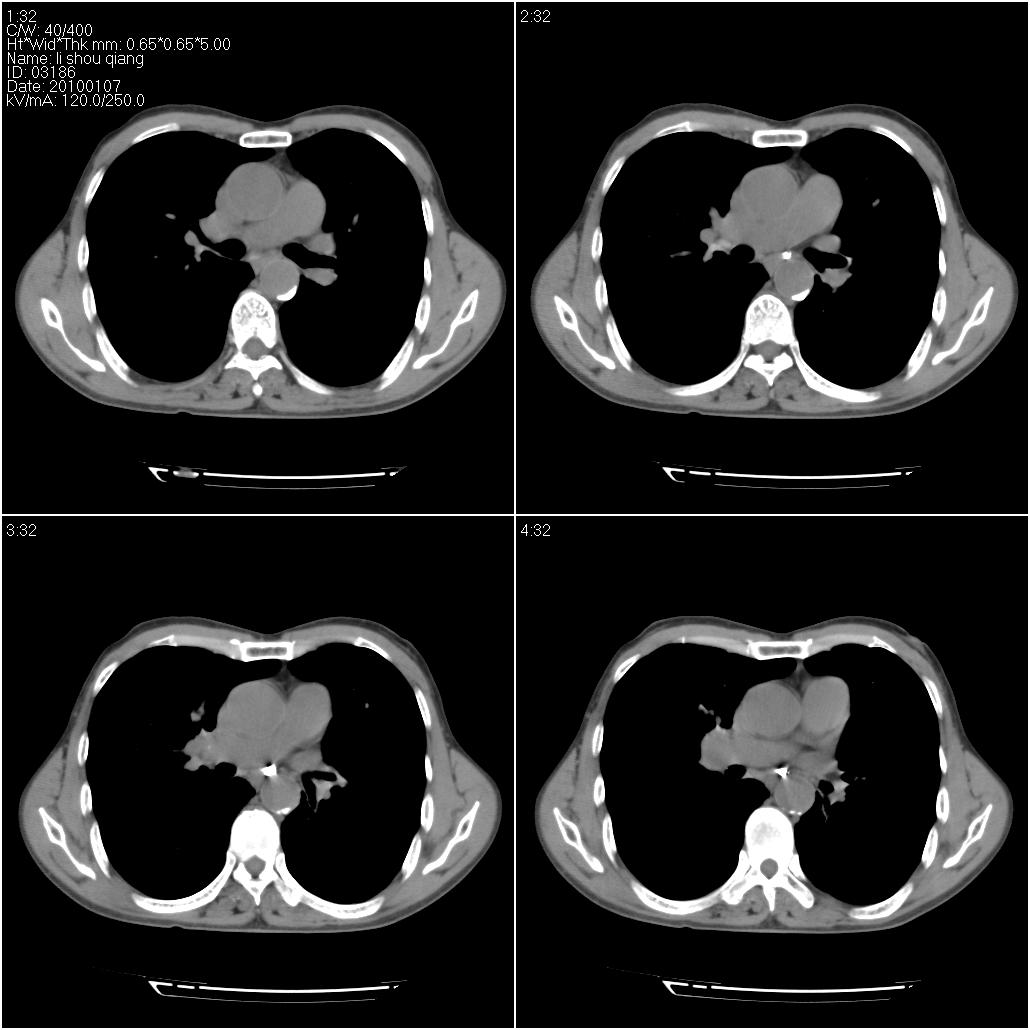

标题: CT24038:男性,58岁。主因咳嗽带血性CT检查。 [打印本页]

标题: CT24038:男性,58岁。主因咳嗽带血性CT检查。

3、建议增强除外主动脉弓息室样动脉瘤。

右肺中叶外侧段可见团块影,外形不规则,内见空泡征。左下肺见蜂窝状低密度透亮影,部分层面主动脉旁瘤样突出。考虑右肺中叶外围型肺癌可能性大,左下肺支气管扩张,主动脉弓瘤样突出。

考虑右肺癌可能性大,左下肺支气管扩张,主动脉弓瘤样突出?建议增强

3、建议冠状位重建除外主动脉弓息室样动脉瘤。